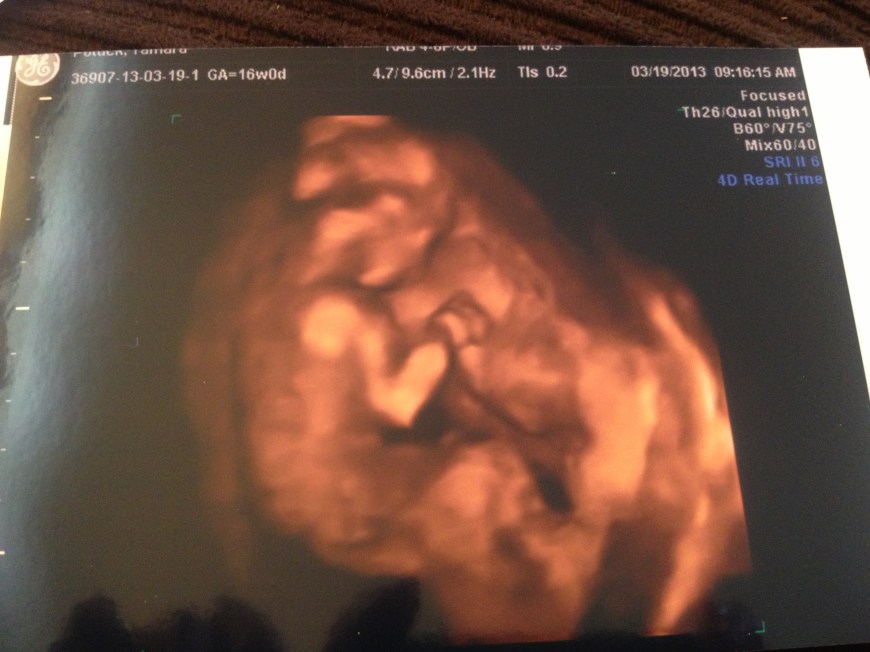

Our little baby girl!

Here she is shying away from the camera! A shy girl for now…